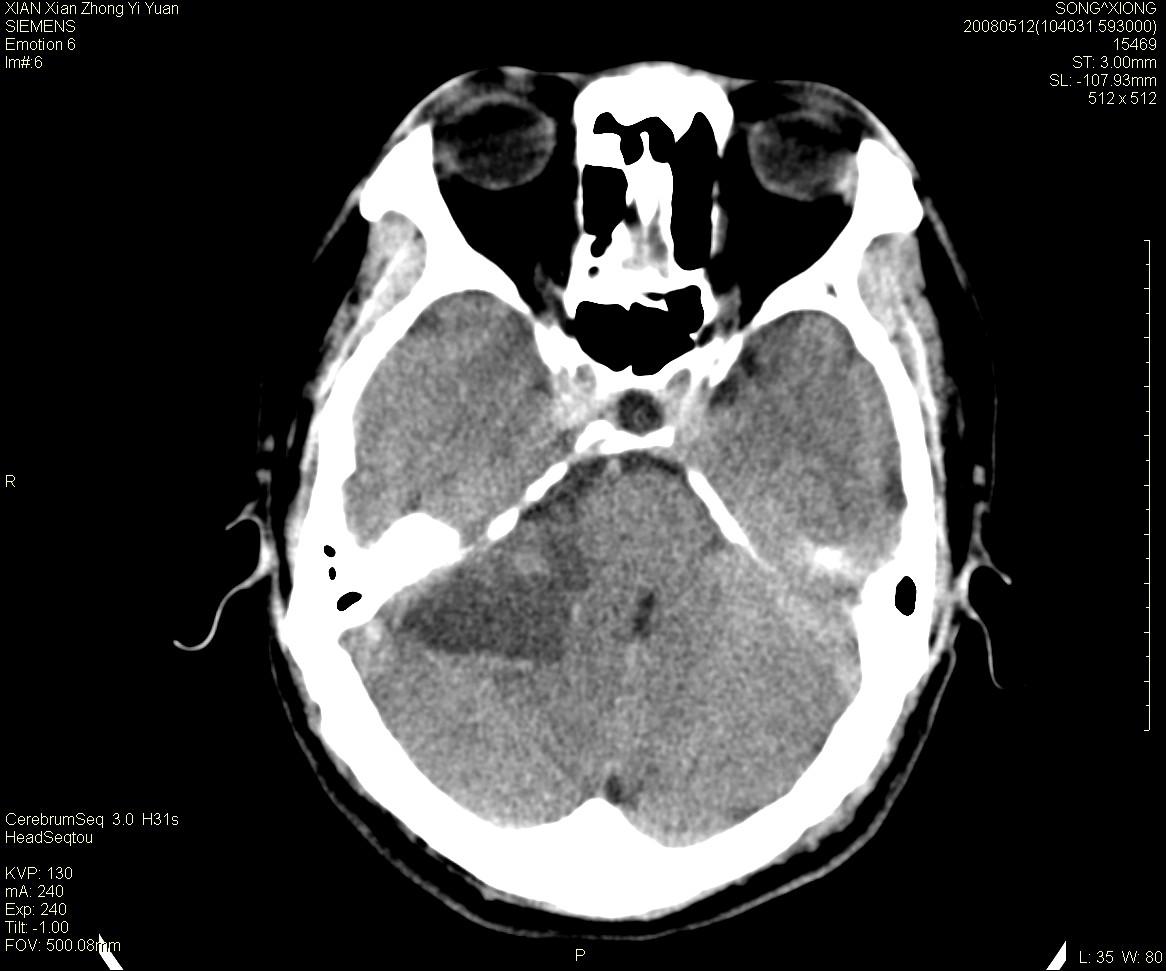

右侧内耳道慢性增宽,内耳道口出可见稍高密度影,桥小脑角池可见以较大低密度影,内缘较清,小脑、脑干、第四脑室受压、移位。

考虑:听神经瘤。

典型的右侧听神经瘤。